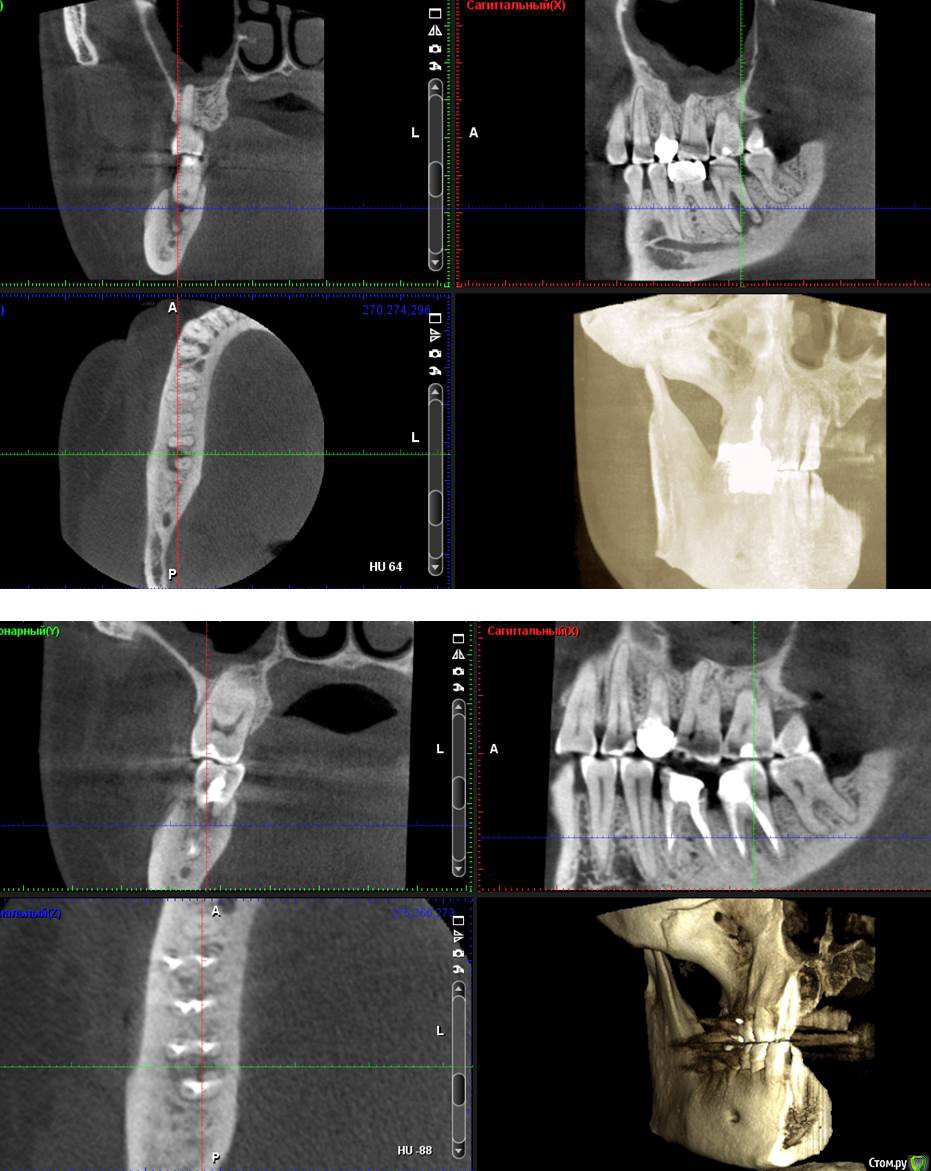

Сева северный Опубликовано 21 апреля, 2016 Поделиться Опубликовано 21 апреля, 2016 (изменено) .Хотелось бы выслушать мнение по зубу 4.6Пациент пришел по рекомендации, коллеги, из сторонней клиники. . Как бы вы поступили в данной ситуации? ( Скриншоты КТ, прилагаются) Изменено 21 апреля, 2016 пользователем Сева северный Ссылка на комментарий

Сева северный Опубликовано 21 апреля, 2016 Автор Поделиться Опубликовано 21 апреля, 2016 (изменено) Мужчина. Возраст: около 50,Жалобы. на болевые ощущения ..отсутствуют. Зуб ранее лечен, имеется старая пломба с нарушенным прилеганием, по границам- кариес. Пальпация, перкуссия безболезненна, в области бифуркации при надавливании, появляется жидкость, желтоватого цвета. При зондировании зонд погружается в межкорневое пространство примерно на 15 мм. Изменено 21 апреля, 2016 пользователем Сева северный Ссылка на комментарий

Гарриевич Опубликовано 22 апреля, 2016 Поделиться Опубликовано 22 апреля, 2016 на трещину не похоже, я бы лечил как банальные периодонтит Ссылка на комментарий

Сева северный Опубликовано 26 апреля, 2016 Автор Поделиться Опубликовано 26 апреля, 2016 Пошаманили .... через 3.5 месяца. Ссылка на комментарий

Сева северный Опубликовано 27 апреля, 2016 Автор Поделиться Опубликовано 27 апреля, 2016 (изменено) Это надо в Вк запостить, для удаляторов)Да там такого много. Вопрос удаления. конечно рассматривался... Но для имплантации, потеря зоны костной перегородки в зоне бифуркации, достаточно критична. Поэтому.. приняли решение эндосанации . (повыращивать кость), а в случае успеха обойтись без нее. Как показывает практика, большие очаги, особенно если не ступала ((((нога стоматолога , с гипохлоридом, быстро... схлопываются. Изменено 27 апреля, 2016 пользователем Сева северный 2 Ссылка на комментарий